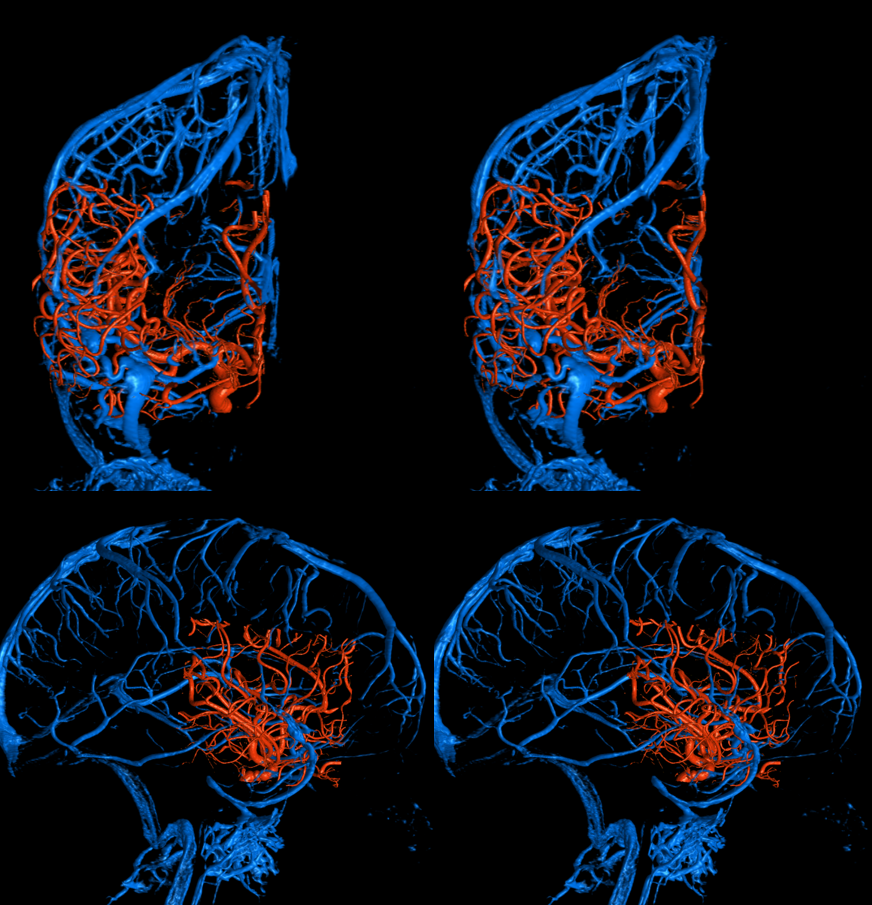

Stereo ICAs

Common venous

Stereo fused VRs. The paracavernous sinus receives deep sylvian (middle cerebral) vein parallel and below the M1 segment, draining via the ovale into the pterygopalatine venous plexus. This is an extremely common drainage pathway for all 3 — cavernous, paracavernous, and laterocavernous.